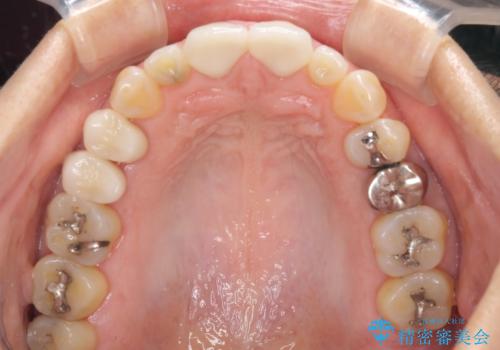

今回はまず欠けた場所を修復して見た目を回復させたのち、ラミネートべニアの仮歯をつくり、しばらく使用して考えて頂きました。メリットやデメリットを説明した結果、外れにくいセラミッククラウンをご選択頂きました。

咬み合わせや元のご自身の歯の色に特徴があったため、セラミッククラウンを修正したり、隣の歯を金属を外して白いつめものに変えたりして経過観察を長めに行いました。

右上の歯に関しても、大きな虫歯があったため、前歯の経過観察の間に治療を行いました。

患者様には大変満足して頂きました。